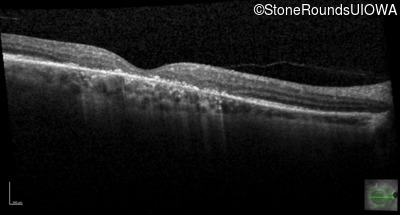

Optical Coherence Tomography - Right - 10/125 +1 sc

Exemplar / OCT Stack